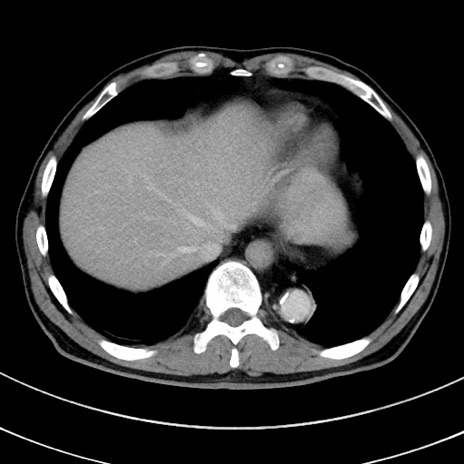

症例8(横断像)

【症例】 60歳代男性

【主訴】 黒色吐物

【現病歴】 4日前から嘔気自覚、2日前の朝食後にも嘔気あり、自分で手で嘔吐反射起こし嘔吐したところ血が混ざっていたため受診。

【既往歴】 5年前汎発性腹膜炎を伴う急性虫垂炎で手術、高血圧、前立腺肥大症、高脂血症

【身体所見】 腹部正中に手術癩痕あり 腹部平坦・軟圧痛なし膨満感あり

【データ】WBC 8400、CRP 4.54